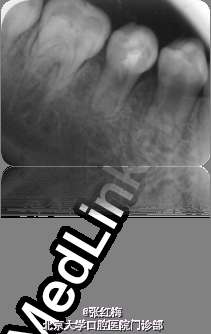

45牙合面充填体完好,边缘密合,叩痛(+),松I0,冷热测均无反应,舌侧牙根对应粘膜见1×1.2cm2 脓包扪诊有波动感,X线:发育8-9期,根中下1/3分成两根,根尖孔喇叭状,根尖周低密度影。

在牙髓再生术后1个月,3个月,5个月,9个月复查 1个月x线:45根尖周低密度影缩小,牙根继续发育。 3个月x线:45根尖周未见病变影,根周膜清晰,牙根继续发育。 5个月x线:45根尖周未见病变影,根周膜清晰,牙根继续发育。 9个月x线:45根尖周未见病变影,根周膜清晰,牙根继续发育,已近完成,髓腔缩小。 讨论:由于畸形中央尖一部分有髓角伸入,因此发现畸形中央尖应根据不同情况给予及时或相应处理。对于圆钝而无妨碍的中央尖可以不做处理。尖而长的中央尖容易折断或被磨损而露髓.可在麻醉和严格消毒下将此尖一次磨除。制备洞形,盖髓充填。还有一种方法树脂在牙尖周围加固防折,使畸形尖随牙齿一同发生生理磨耗,促使髓角形成修复性牙本质,可用于尚未建合的牙。短期内折断的畸形中央尖无牙髓根尖炎症状,且牙髓活力正常者,备洞盖髓充填。折断的畸形中央尖有牙髓炎根尖炎者,往往牙根未发育完成,需做根尖诱导形成术,或牙髓再生治疗。 牙髓坏死或者根尖炎年轻恒牙的牙髓治疗方法有:根尖诱导成形术,MTA根尖封闭技术,近年来的牙髓再生技术。 根尖诱导成形术,所用根管内充填材料是氢氧化钙及其制剂,诱导根尖周的组织在根尖部形成钙化屏障。需要多次复诊和更换根充药物,疗程较长,增加了根管再次污染的可能性,并不是所有都能形成根尖部的钙化封闭。而且根管壁仍然薄弱,增加了远期根折的风险。 MTA具有良好的生物相容性和封闭性,MTA根尖封闭技术中用其特性封闭根尖,防止充填材料在根尖部的外溢。生物相容性好,可以诱导矿化,但其完全固化需要较长时间,不易操作,抗菌效果不确定,价格昂贵。 牙髓血管再生术通过在操作中彻底有效的根管消毒,尽量保护牙髓干细胞和牙乳头间充质干细胞,并为这些干细胞的增殖和分化提供良好的环境,这些干细胞在信号分子和盖髓剂矿物三氧化物凝聚体(mineral trioxide aggregate,MTA)的诱导下,可以分化为成牙本质细胞和成牙骨质细胞等,从而在牙根继续发育中发挥着重要作用。研究表明,在坏死感染的年轻恒牙根管内进行成功的血管再生后,其根尖周炎症能愈合且牙根得以持续发育,出现根尖闭合、根管长度增加及管壁增厚等,牙髓血管再生术有可能成为治疗年轻恒牙根尖周炎的新选择。